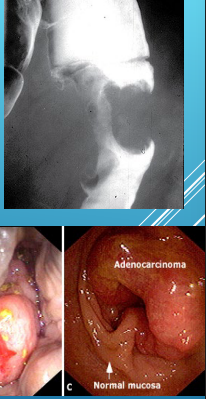

mucosa, biopsy, apple core

Colorectal Cancer: Diagnosis

-Colonoscopy (preferred)

Endoluminal mass arising from ______

Bleeding may be present

______ must be done to confirm diagnosis

-Barium Enema

_____ ____ lesion

-CT colonography